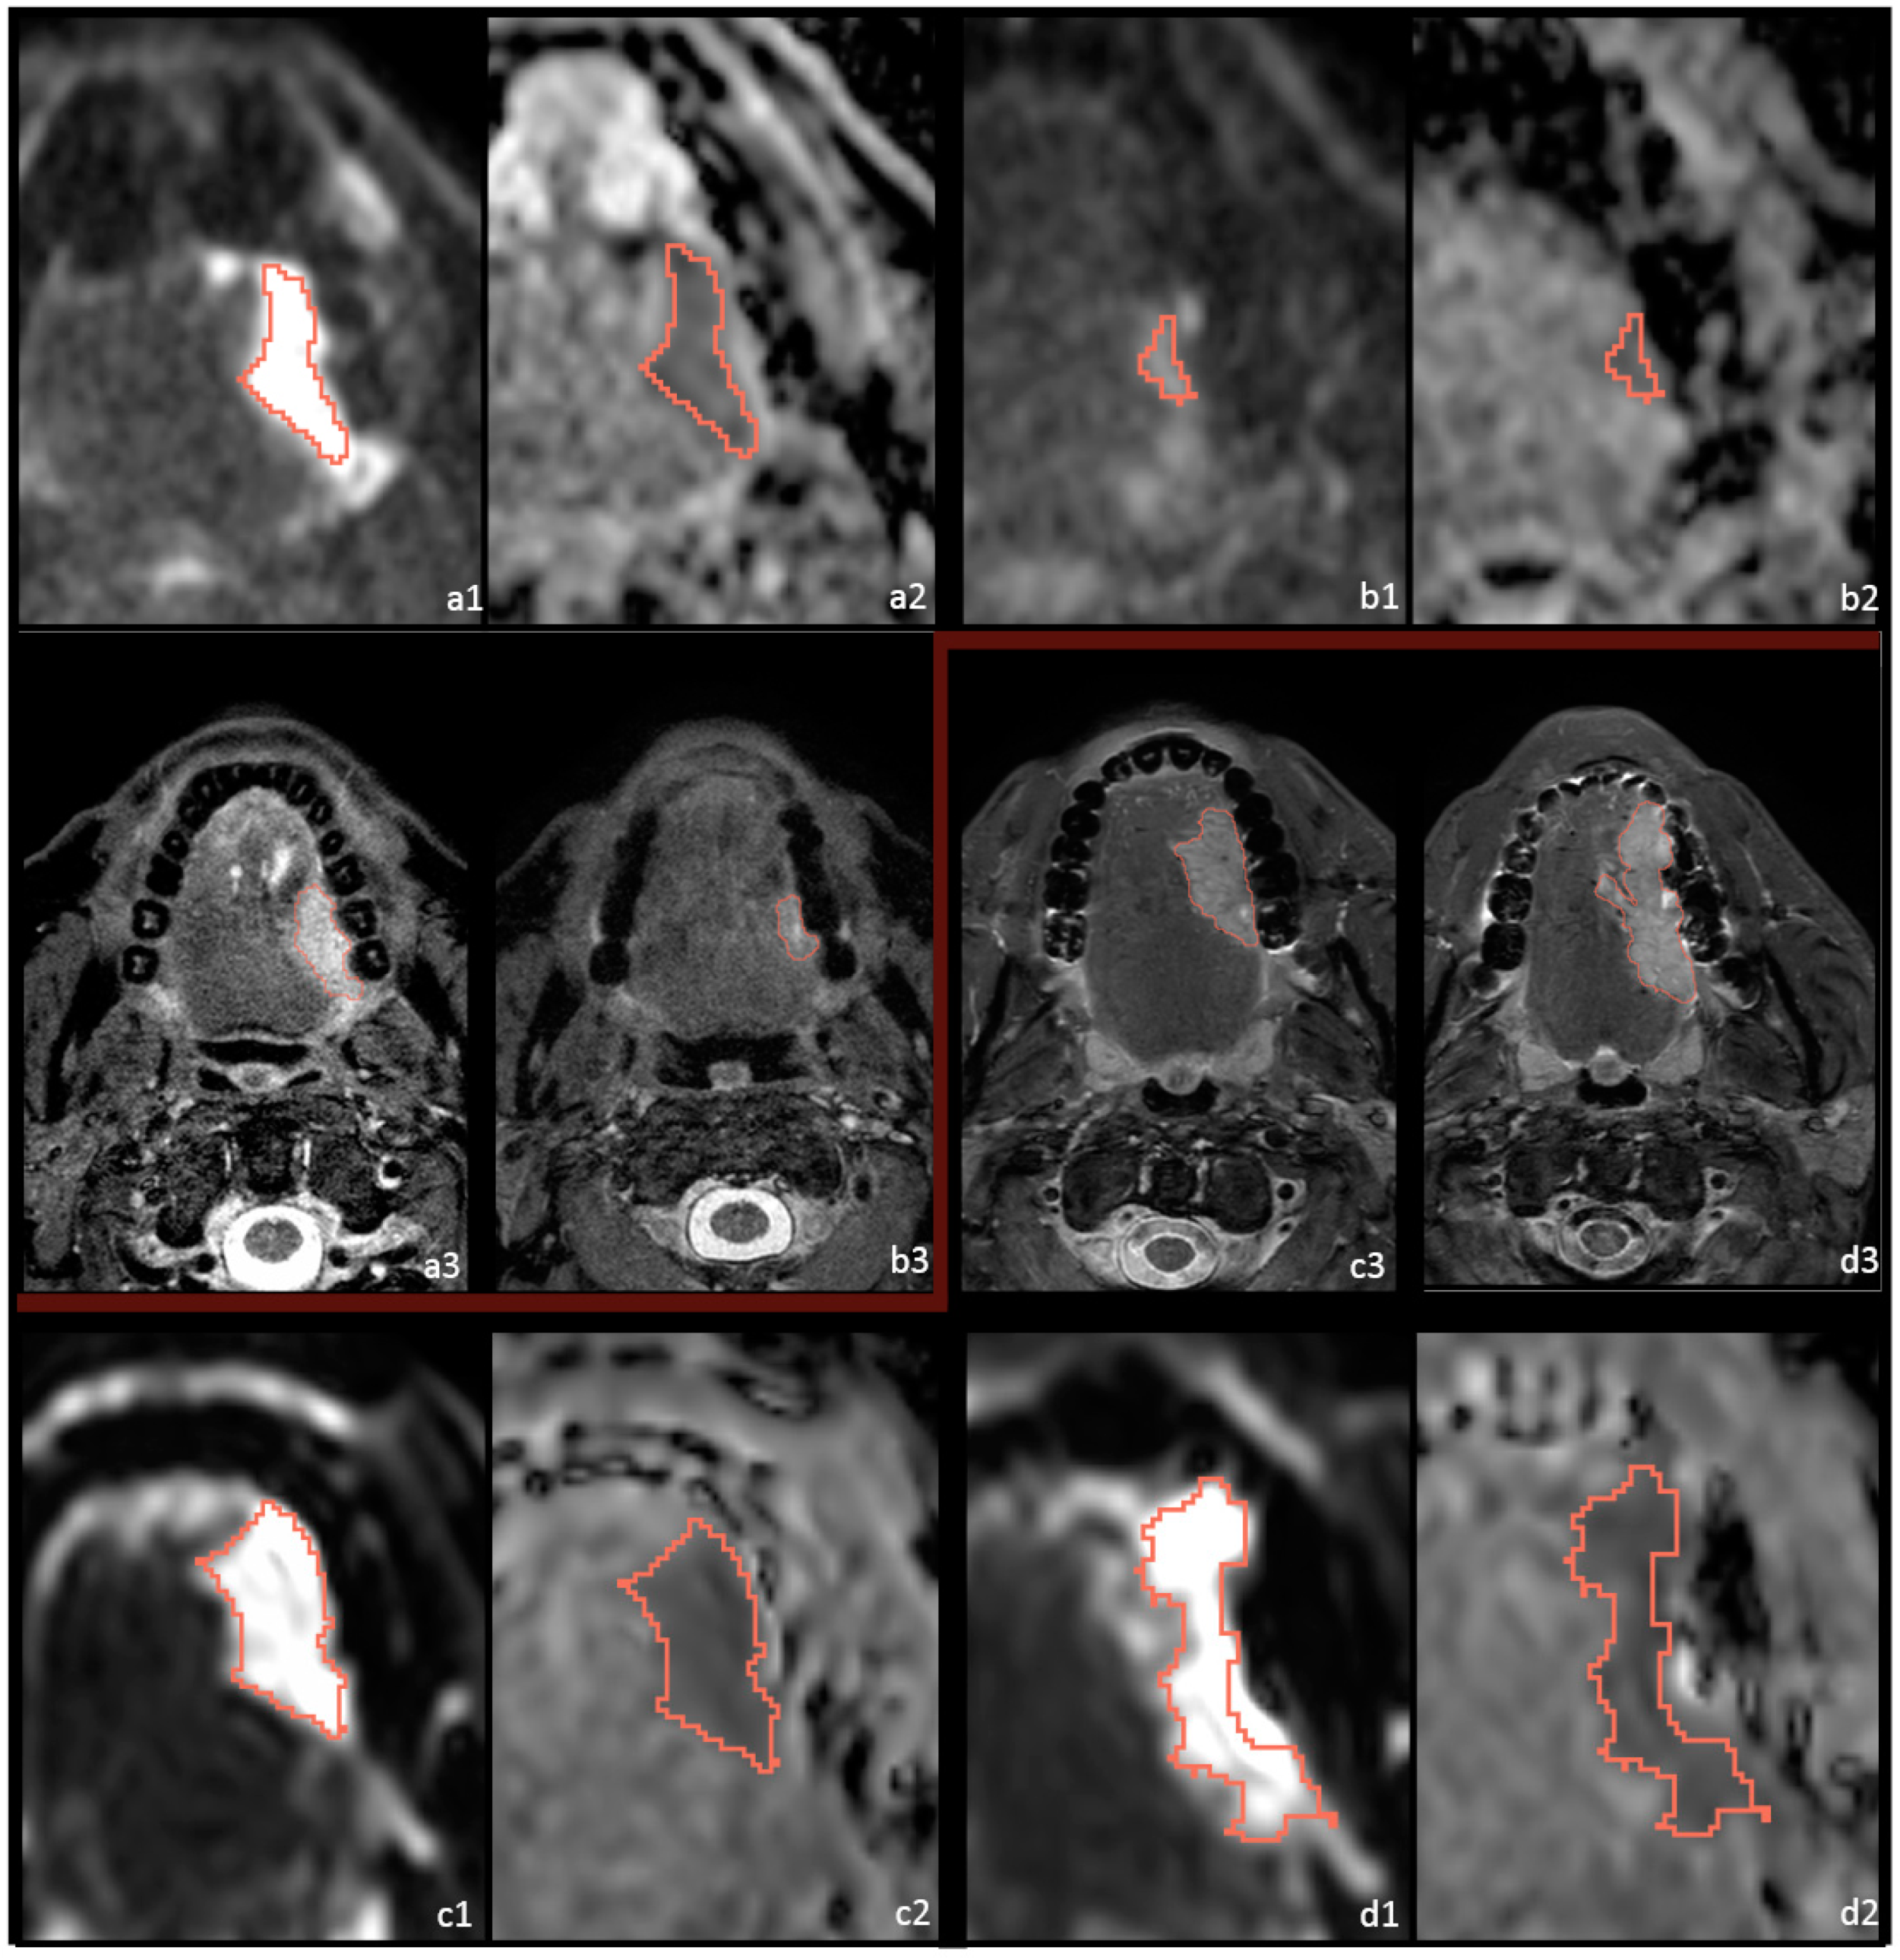

2.3. Postprocessing and Feature Extraction